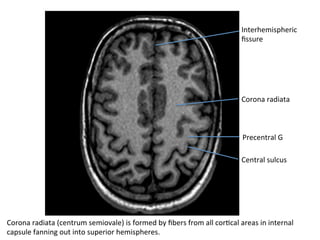

Corona	radiata

Central	sulcus

Precentral	G

Corona	radiata	(centrum	semiovale)	is	formed	by	fibers	from	all	corHcal	areas	in	internal

capsule	fanning	out	into	superior	hemispheres.

Interhemispheric

fissure